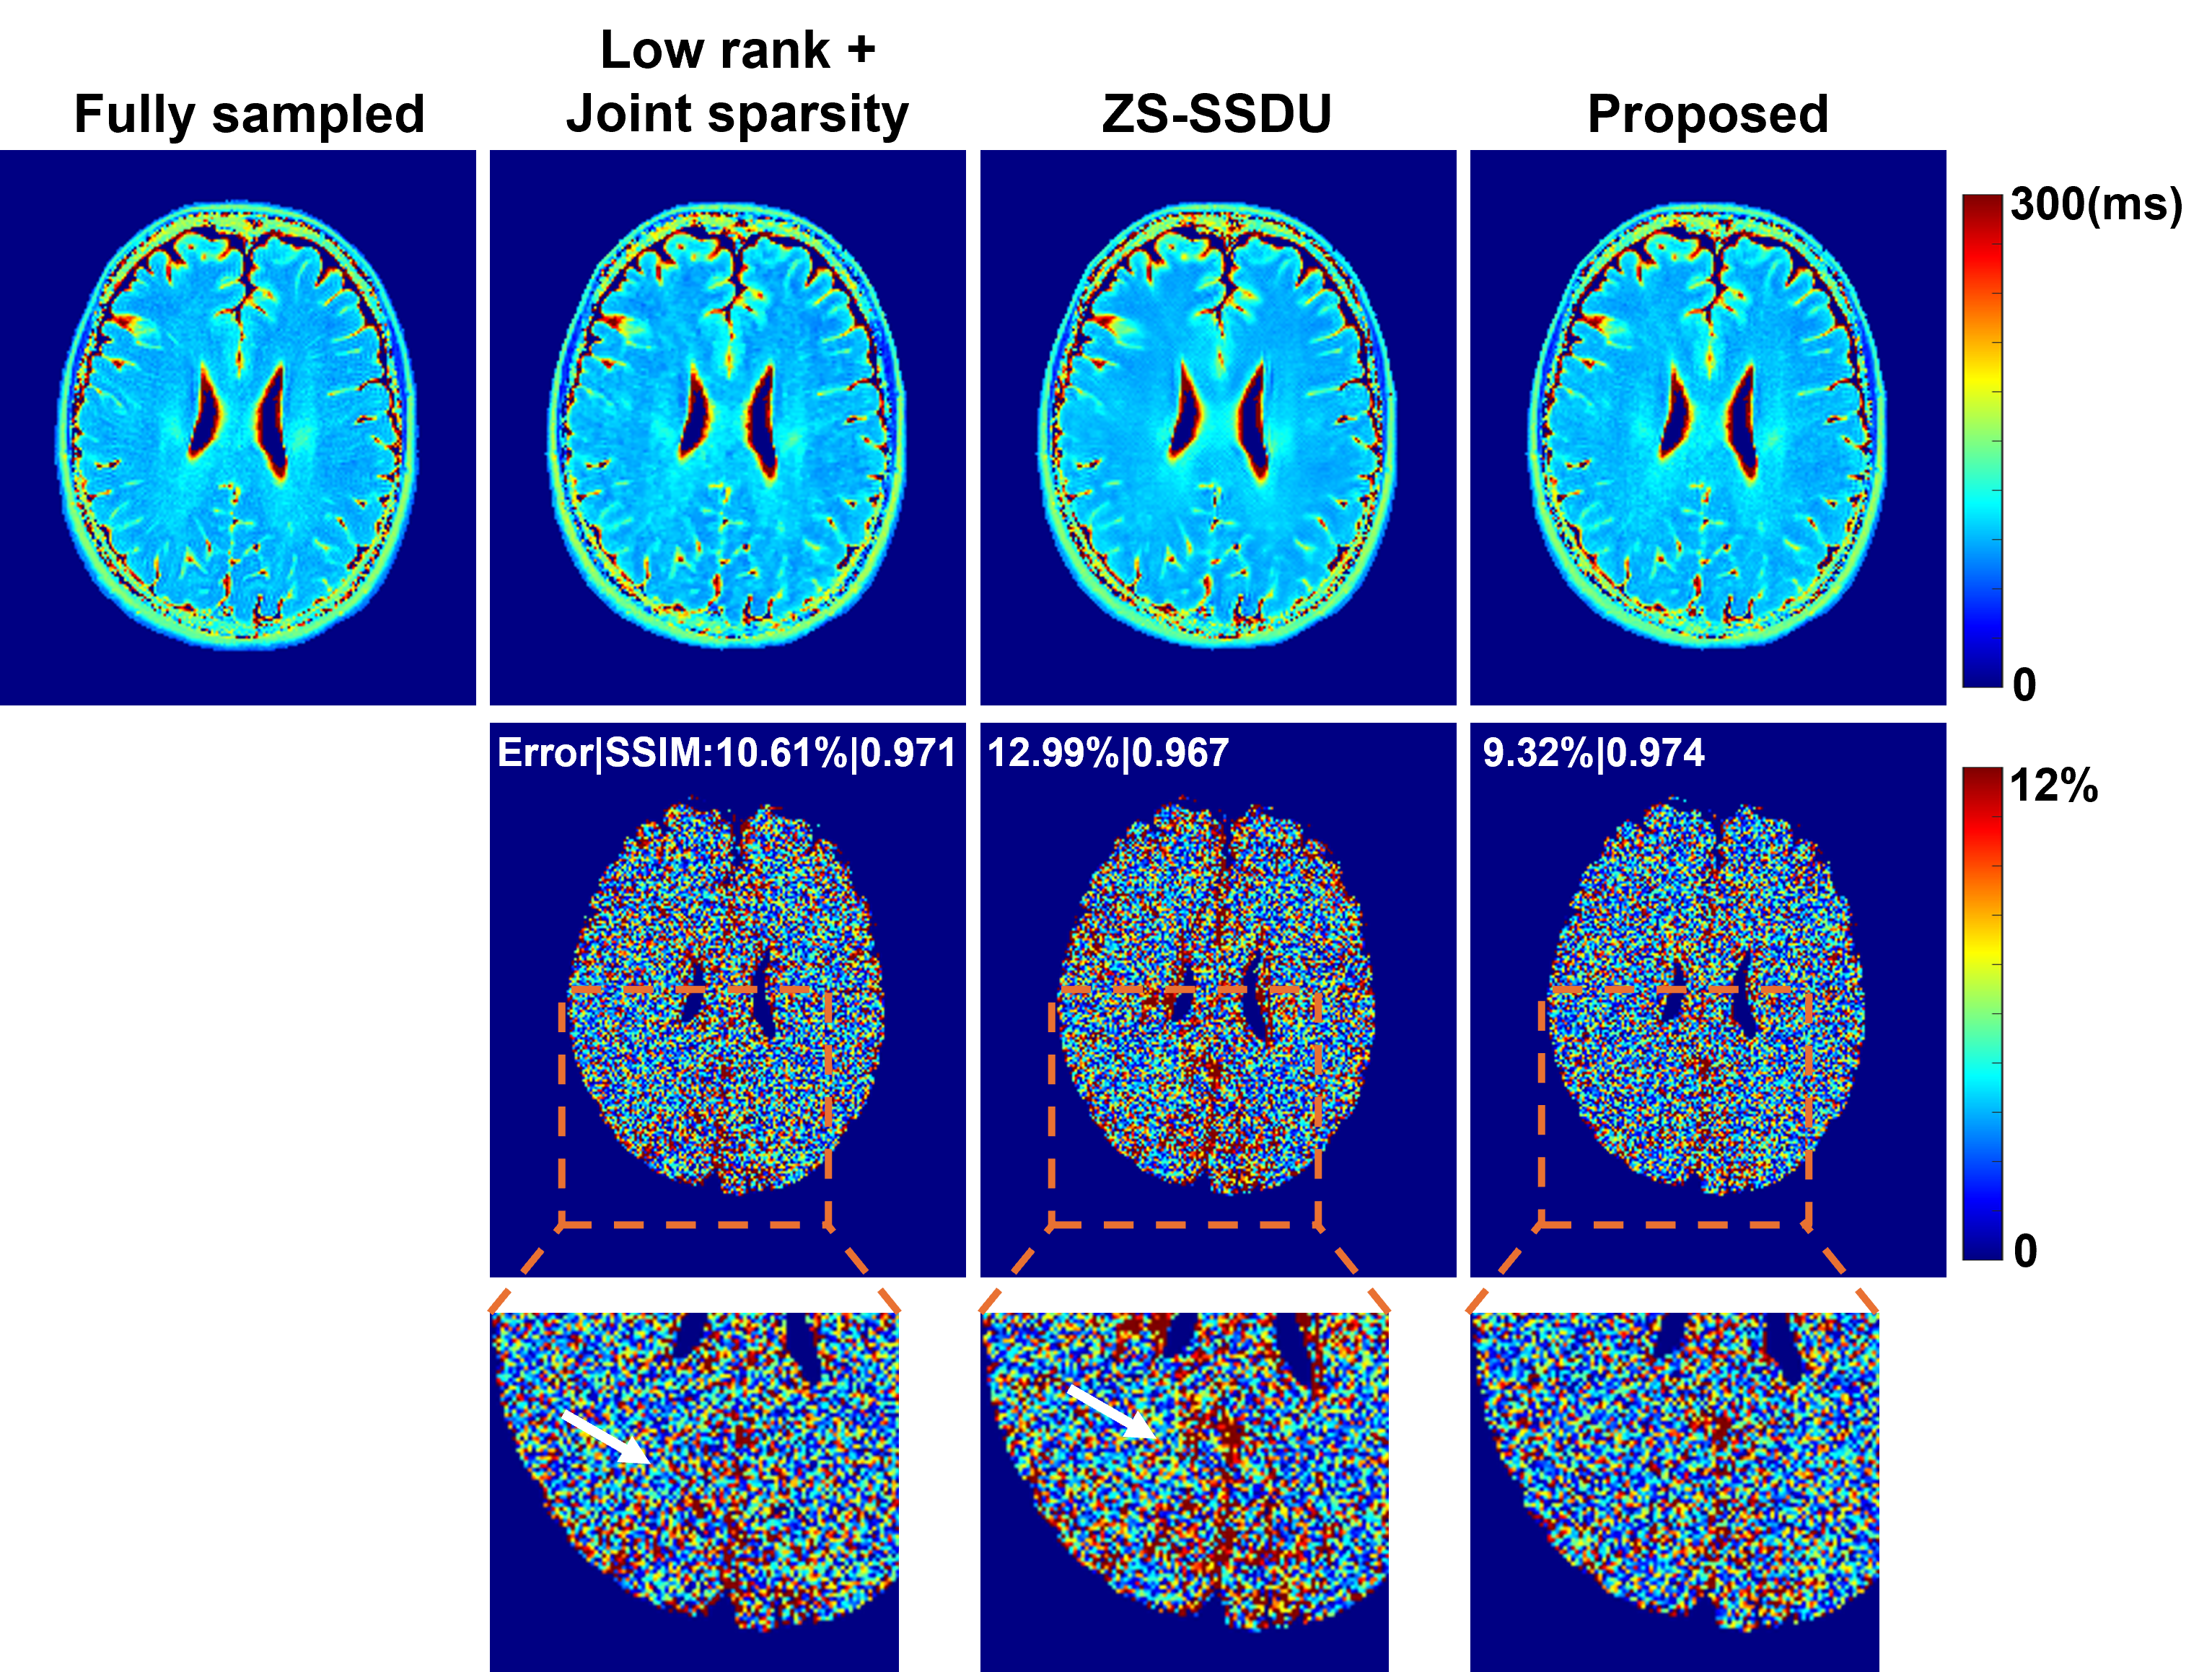

4.3 mapping Results

For mapping, we compared the proposed method with a joint sparsity constrained reconstruction [majumdar2011accelerating] and a state-of-the-art zero-shot self-supervised reconstruction method (ZS-SSDU) [yaman2022zero]. We selected ZS-SSDU as a primary baseline because our method also follows a zero-shot learning paradigm, requiring no supervised re-training or fine-tuning on domain-specific datasets. Representative reconstructed images at AF=6 are shown in Fig. 4. The proposed method consistently produced reconstructions with improved quality and reduced errors across different contrasts (FAs) compared to other methods. The corresponding maps are shown in Fig. 5. The proposed method achieved the most accurate estimates w.r.t. the fully sampled reference as shown by the lowest relative errors and highest SSIM values, effectively suppressing artifacts. The zoomed-in regions further demonstrate a better preservation of structural details by the proposed method. The ZS-SSDU method, although produced lower errors than the joint sparsity method, seemed to result in strong bias in certain localized areas (Fig. 5, last row). These results demonstrated that the proposed representation can work synergistically with zero-shot self-supervised learning, leading to improved reconstruction and quantification performance. More quantitative comparisons under different AFs are shown in Fig. 7.